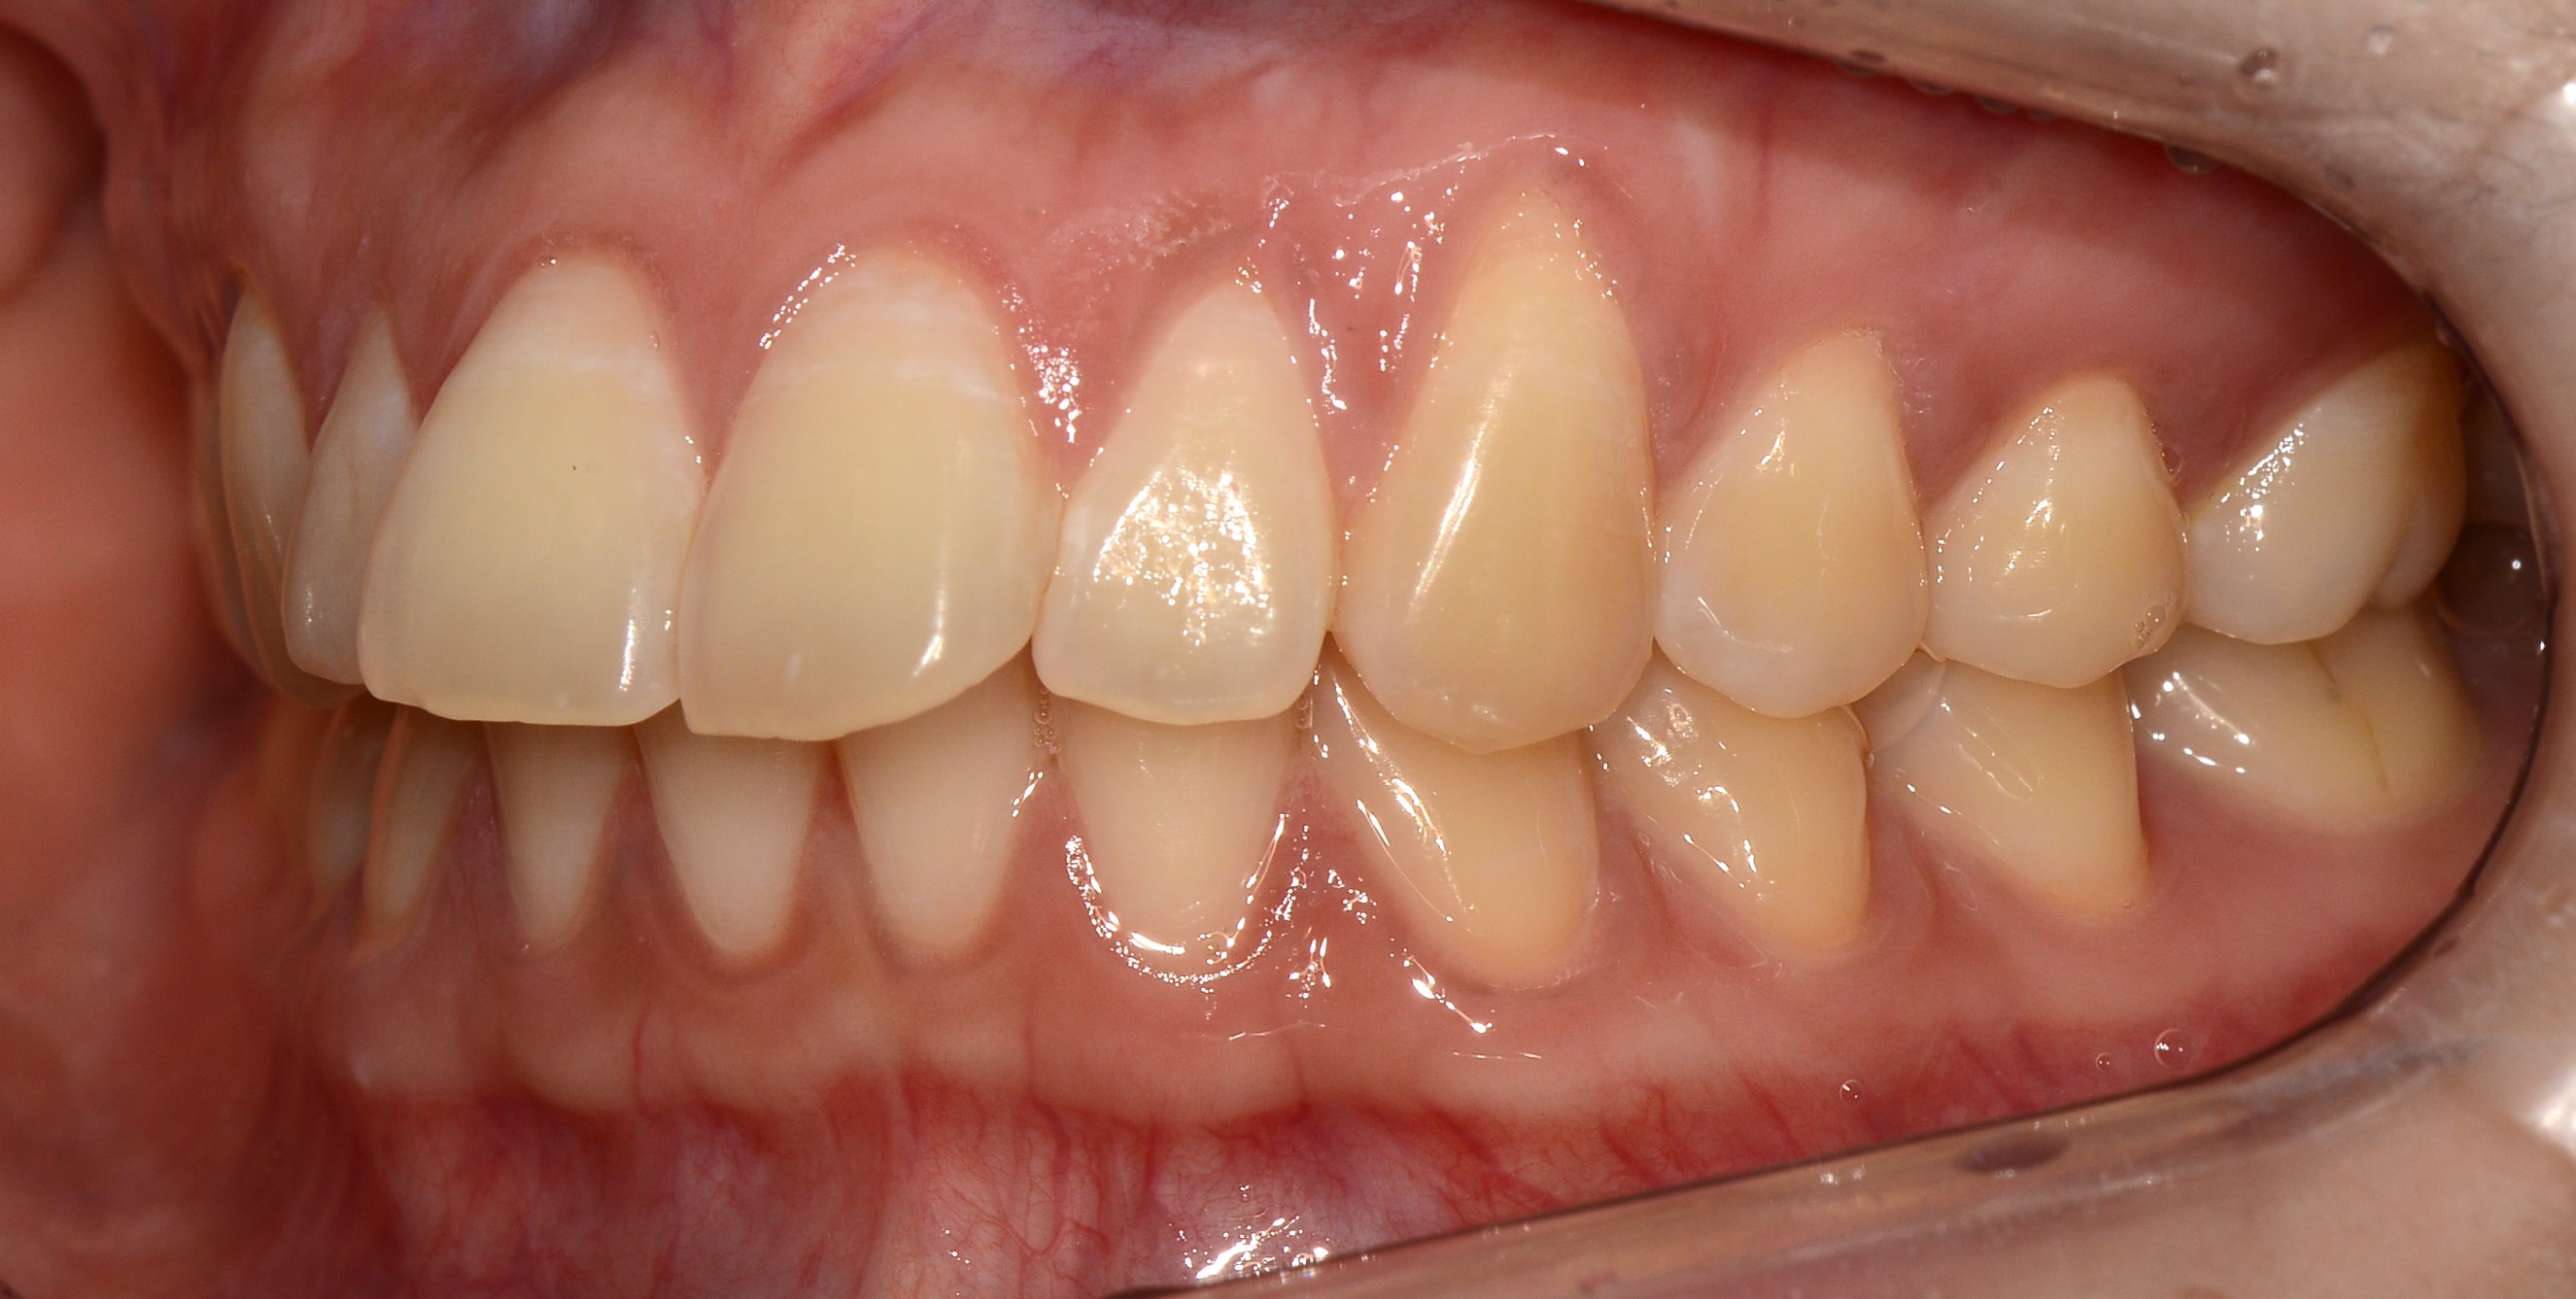

치료 후 사진입니다.